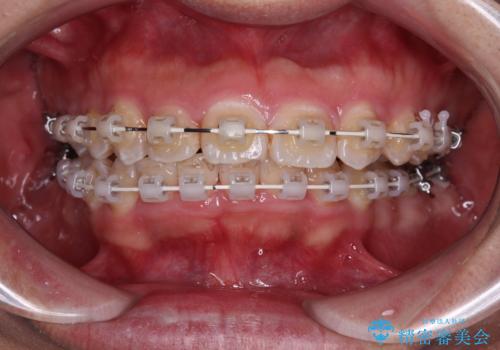

- 矯正装置

- 審美装置

- 2年5ヶ月

- 10-30回